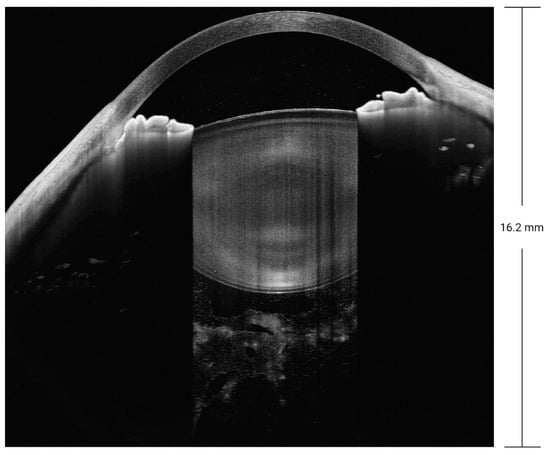

SS-OCT not only enables the examination of the cornea, anterior chamber angle, and iris, as with the previous generations of anterior segment OCT, but also allows the visualization of the entire crystal lens and the vitreous behind it. It yields an unprecedented imaging depth of 16.2 mm for the anterior segment, as demonstrated in Figure 8. SS-OCT examination is faster and more reproducible than previous generations of OCT. For patients with ocular trauma who cannot be examined using ultrasound biomicroscopy, SS-OCT can be used to discover small injuries to the lens and iris that may be overlooked when using slit-lamp examination.

Figure 8.

SS-OCT with a depth of 16.2 mm for the anterior segment.